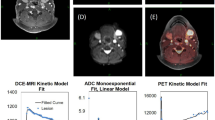

Of those 48 lesions missed by DWI, 20 were malignant (nine tumors [seven recurrent and two primary], nine recurrent lymph nodes, and two metastasis). Fourteen lesions of those 20 (six tumors, six recurrent lymph nodes, and two metastasis) were missed based on technical issues (artifacts). The remaining six malignant lesions (three tumors and three recurrent lymph nodes) did not show restricted diffusion (Fig. 1).

DWI added 20 lesions to the PET/MRI findings, and of those, 11 were inflammatory/reactive lymph nodes and nine were malignant lymph nodes. However, none of these nine malignant lymph nodes changed the overall staging since other lymph nodes defining the N-stage were already detected in PET/MRI without DWI (Fig. 2).

a–c Sixty-nine-year-old man with squamous cell carcinoma of the base of the tongue. a Axial T2w, Axial ceT1w, DWI, ADC, and PET/MRI showing the primary tumor in the base of the tongue. b PET/MRI in different levels showing seven metastatic lymph nodes. c DWI (top) and ADC map (bottom) in different levels showing nine metastatic lymph nodes. In both PET/MRI and DWI, N-staging remains N2c

Concerning the quantitative values of PET and DWI, there was a significant difference (p = 0.001) in SUVmax and SUVmean between malignant and non-malignant lesions (10.5 vs 6.6 and 6.4 vs 4.1, respectively). ADCmean as well as b-valuemean and b-valuemax showed no statistical significant difference between those lesions (Table 6).